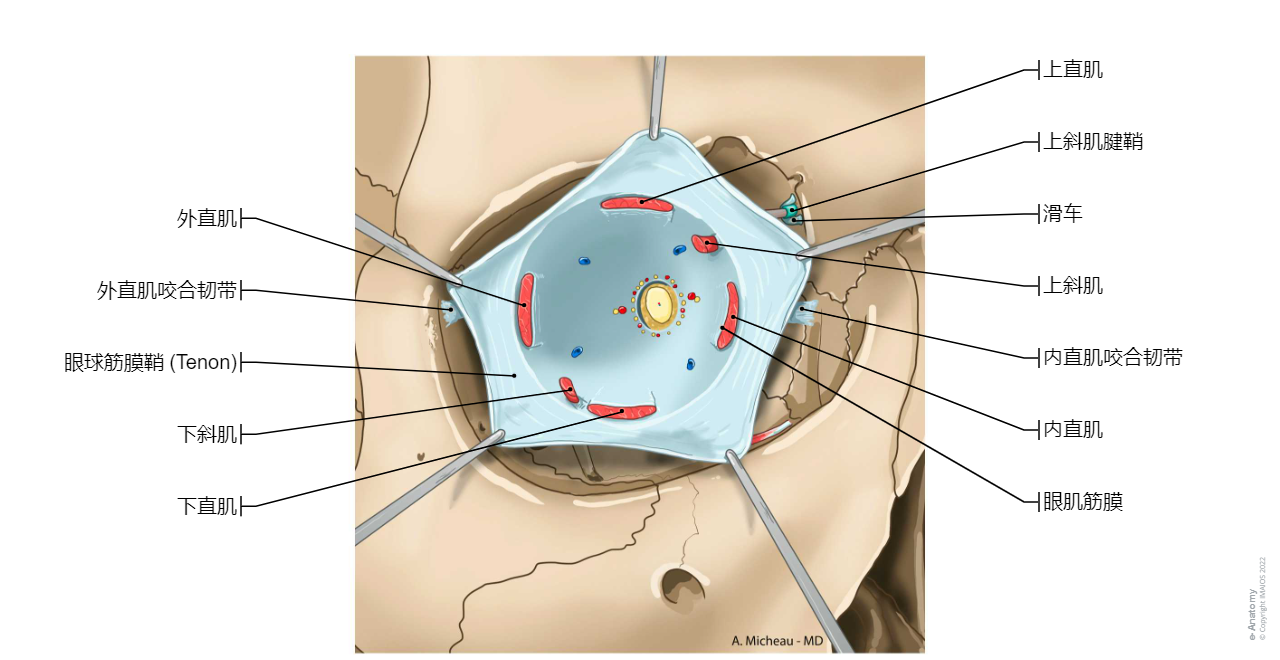

眼球筋膜-眼眶

眼球筋膜-眼外肌

眼球筋膜